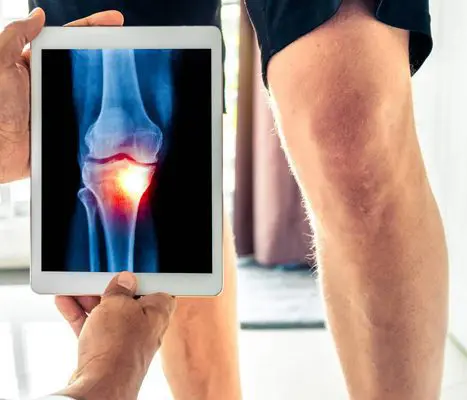

Diagnosestellung Kniearthrose

Zur Diagnose der Arthrose sind der Krankheitsverlauf, die klinische Untersuchung und ein Röntgenbild entscheidend. Im Röntgenbild zeigt sich der Knorpelverschleiss durch die Verschmälerung des Gelenkspalts. Die Aufnahmen werden unter Belastung des Gelenks im Stehen gemacht, zusätzlich wird die gesamte Beinachse untersucht. Bei Bedarf können „Stressaufnahmen“ zur Beurteilung der Bandstabilität und des Kniezustands angefertigt werden.